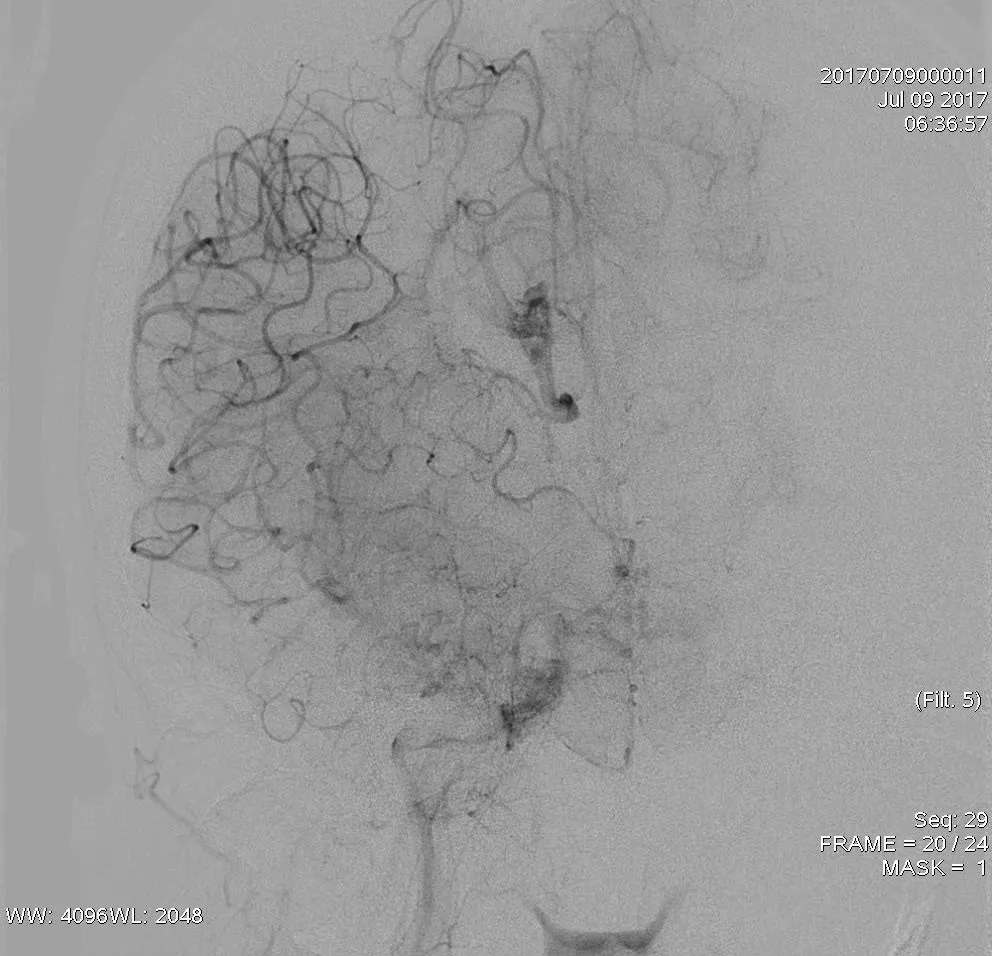

双支架放置后造影提示,右侧ACA部分显影,MCA仍血管显影不佳(A),双支架放置4分钟后造影提示,右侧前循环显影更差(B)

最后双支架联合抽吸拉通血栓。造影提示取栓后血管再通,TICI 3级。

造影提示取栓后血管再通,TICI 3级(A);抽吸联合取出的血栓(B)